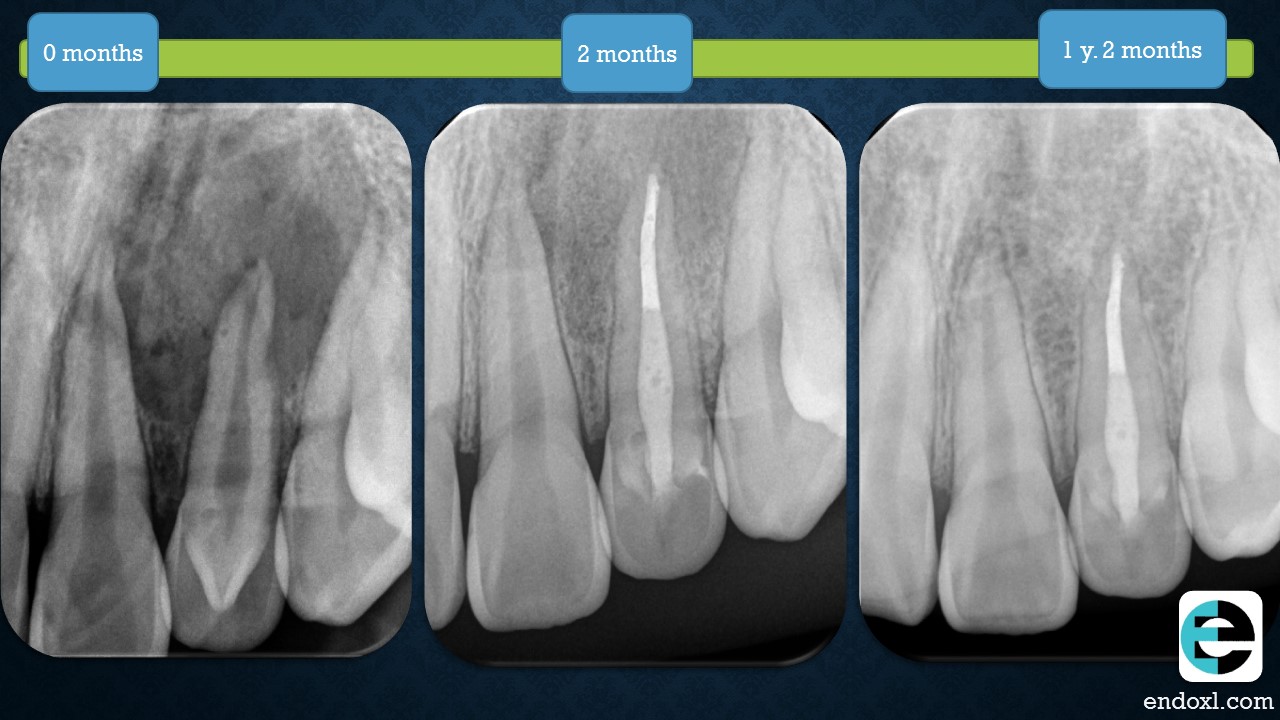

Intriguing dental journey Rajiv Patel. Following the 15 yom recovery with keen interest. Your dedication to multiple visits and strategic treatments is commendable.